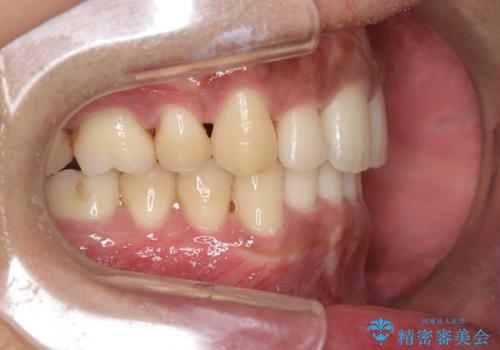

- 前歯のデコボコ(叢生)と、上下の歯の重なりが深い「ディープバイト(過蓋咬合)」を主訴にご来院されました。精密検査の結果、歯が並ぶスペースが不足しているため、上顎左右の小臼歯を抜歯することでスペースを確保し、全体の咬み合わせを改善する治療計画を立案しました。これにより、見た目の改善だけでなく、過度な咬み合わせによって生じる歯や顎への負担も軽減することを目指します。

今回の矯正治療では、まず歯が並ぶスペースを確保するため、上顎の小臼歯を抜歯しました。抜歯によってできたスペースを利用して前歯を奥へ移動させ、デコボコを解消。同時に、奥歯の咬み合わせを調整することで、深すぎた咬み合わせであるディープバイトも改善しました。治療の結果、長年気にされていた前歯のデコボコが解消され、理想的な歯並びに。さらに、正しい咬み合わせを獲得したことで、機能的にも安定した美しい口元になりました。